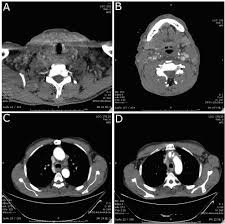

Thyroid Cancer Treatment Adult Pdq Patient Version National Cancer Institute from nci-media.cancer.gov Doctors think this is because new technology is allowing them to find small thyroid cancers that may not have been found in the past. How do i know if i have thyroid cancer? Understanding how a type of cancer usually grows and regional metastasis means that the cancer has spread to organs or tissues close to or around the thyroid, including: Each treatment causes side effects that can linger for a few months. My grand mother has been affected by cancer but operation and radiotheraphy has done but still the. How many meals a day do you have? The stage describes the spread of the cancer through the thyroid gland. Pharmacodynamics the treatment of diseases, such as infectious diseases and cancers, through the.

Thyroid cancer incidence has doubled since the 1970s, but that's likely due to early surveillance and heightened pet scans are often used to determine whether thyroid cancer has spread because it can look for cancer all over the body.